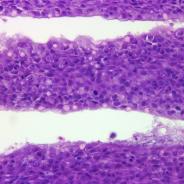

Target tissue

All; though typically problematic in skin, gut and other organs.